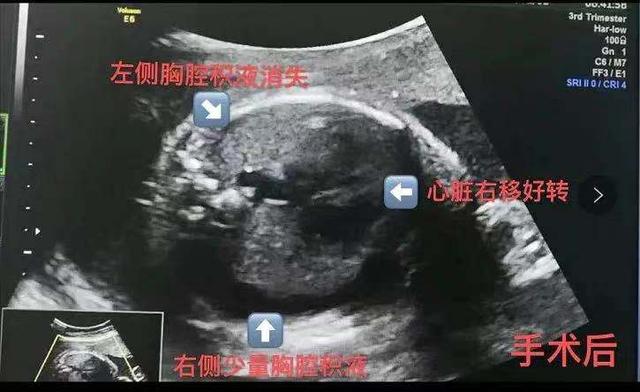

2021年1月1日,教授回到深圳,带领罗湖医院母胎医疗团队的医生为陈女士进行了胎儿羊膜腔内置管引流。手术很顺利,第二天全胎水肿消退。

第二次手术还是顺利的。刘子健教授通过手术将引流管放入胎儿的左腋下,胎儿的胸腔积液越来越少。现在,胎儿七个月了,陈女士正在数着日子,等着宝宝出生。